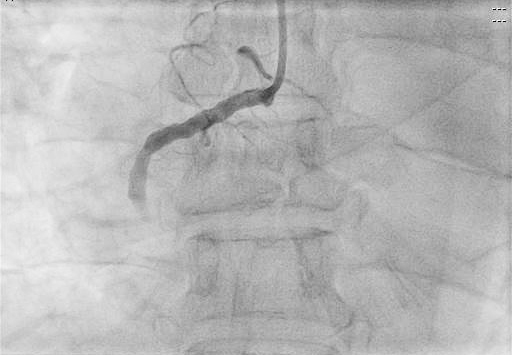

術(shù)前

患者進(jìn)入導(dǎo)管室后,憋喘明顯,血壓、氧飽和度低,需面罩吸氧、大劑量去甲腎上腺素維持血壓。朱宗濤主任建議應(yīng)使用強(qiáng)支撐指引導(dǎo)管,先用軟導(dǎo)絲輕柔操作,結(jié)合血管內(nèi)超聲(IVUS),嘗試尋找血管真腔。術(shù)中選擇6F SAL指引導(dǎo)管行冠狀動(dòng)脈造影提示右冠中段閉塞,先后嘗試Anyreach、Sion工作導(dǎo)絲未能通過(guò)閉塞病變,然后在Finecross微導(dǎo)管輔助下,換用Gaia1硬導(dǎo)絲通過(guò)閉塞處成功送至右冠遠(yuǎn)端,行血管內(nèi)超聲(IVUS)檢查顯示血管支架遠(yuǎn)段局部夾層、血腫,導(dǎo)絲全程位于血管真腔,在IVUS精確定位下,成功開(kāi)通血管并植入支架2枚。術(shù)后,經(jīng)CCU醫(yī)護(hù)人員的精心治療,已于10月10日康復(fù)出院。